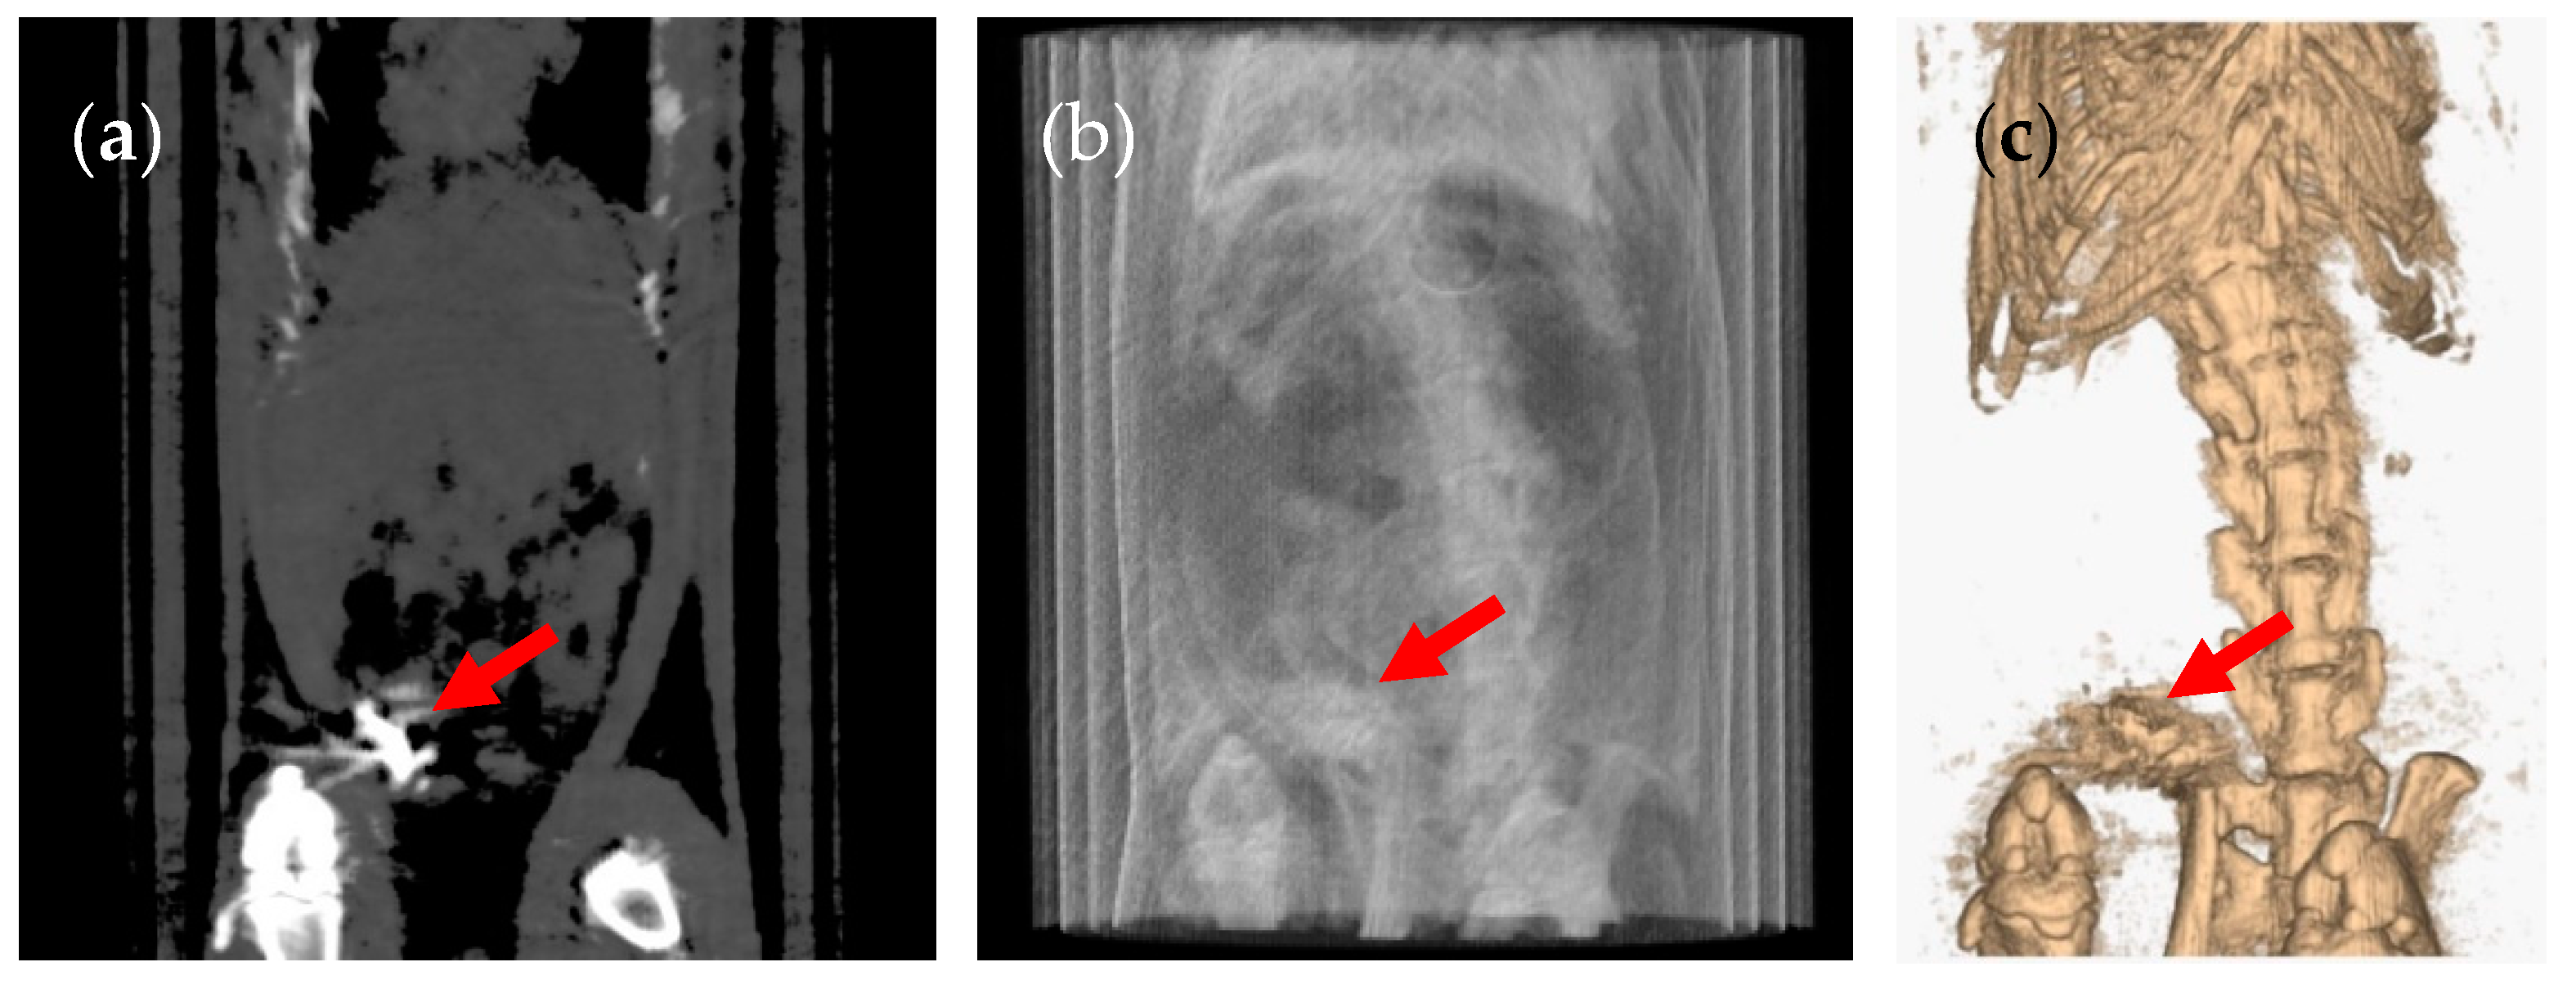

3. Results and Discussion